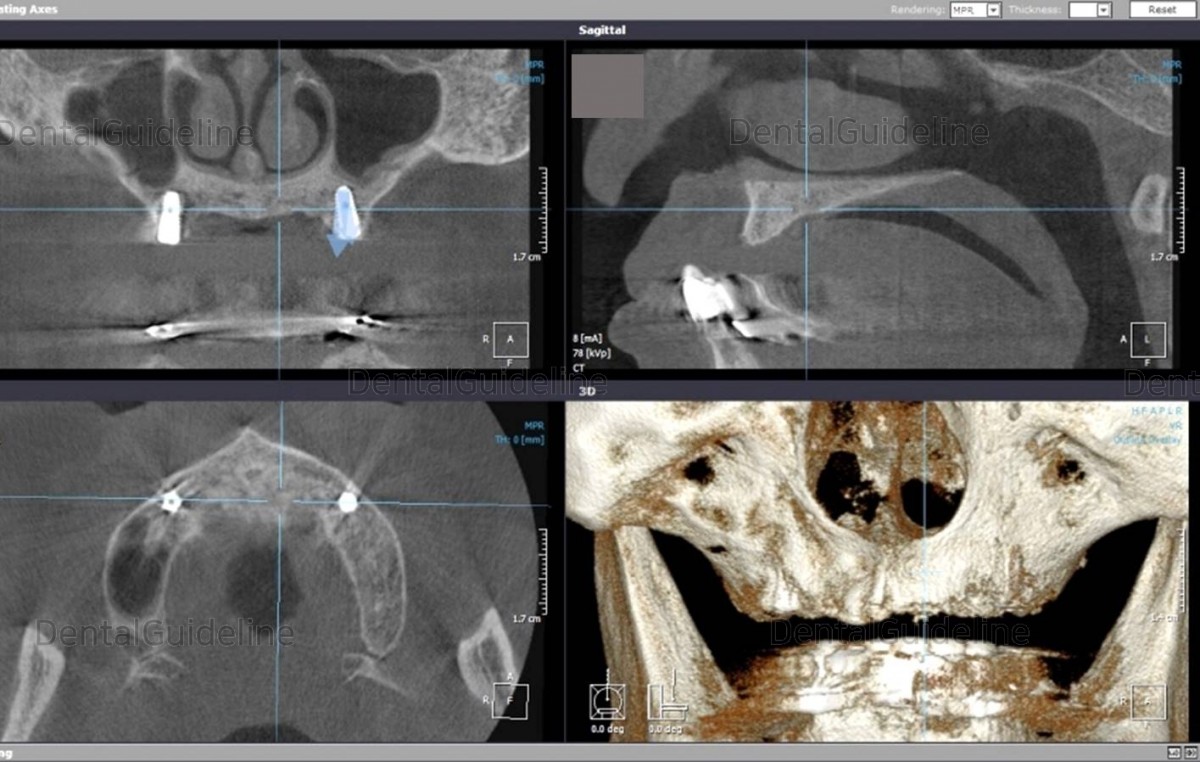

Check the angle between the two implants on the radiograph